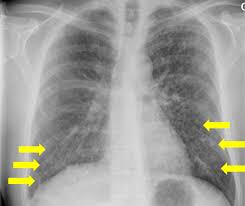

• CXR: bilateral interstitial opacities

Imaging patterns of Pneumocystis jirovecii pneumonia in HIV-positive and  renal transplant patients – a multicentre study | Swiss Medical Weekly